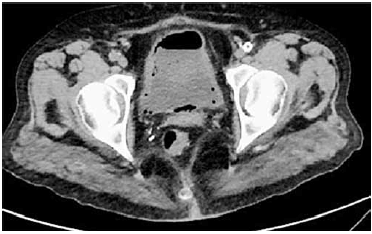

Paciente diabética, portadora de IRC em programa de diálise, apresenta ITU de repetição por Escherichia Coli.

Na CT de bexiga sem contraste, foi encontrado o seguinte diagnóstico: